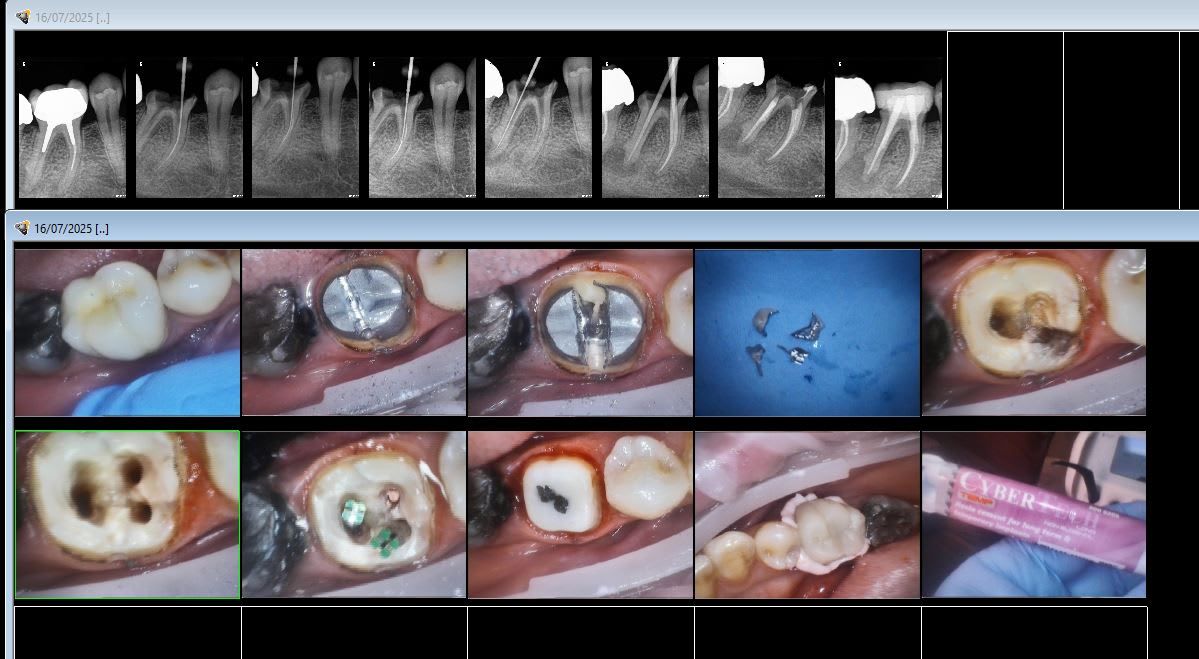

Tac tac boum boum.

NB : T’aurais au moins pu mettre un coup de fraise pour rattraper le profil de l’Ag sur 47.

Provisoire scellée au ciment provisoire "long terme" en attendant de voir si le 4 ième ne revient pas ( je ne retraite que les 4ièmes symptomatiques sinon j'y passerais tout mon temps )

La clavette dans le canal pas alésé, une spécialité bien de chez nous